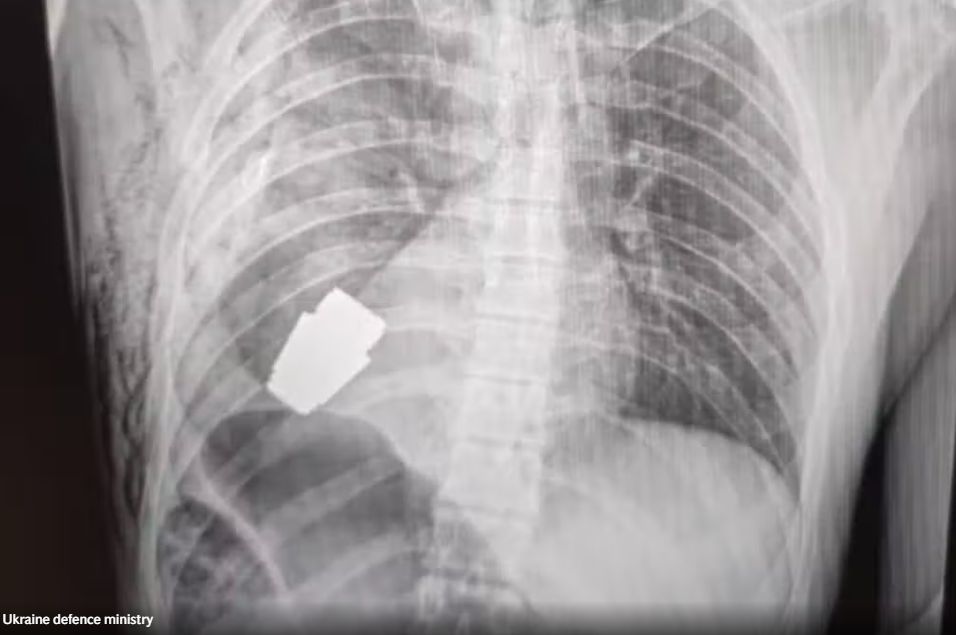

Με μια πρωτοποριακή επέμβαση κατάφεραν να αφαιρέσουν από το στήθος ενός 28χρονου στρατιώτη χειροβομβίδα η οποία δεν είχε εκραγεί.

Η ιατρική ομάδα με επικεφαλής τον γιατρό Andrii Verba πραγματοποίησε μια πολύ λεπτή χειρουργική επέμβαση και μάλιστα χωρίς τη χρήση ηλεκτροπηξίας -ιατρικής τεχνικής που χρησιμοποιείται για τον έλεγχο της αιμορραγίας κατά τη διάρκεια της επέμβασης-, καθώς θα μπορούσε να πυροδοτήσει τη χειροβομβίδα, όπως αναφέρει σε ανάρτησή της η Χάνα Μάλιαρ, αναπληρώτρια υπουργός Άμυνας της Ουκρανίας.